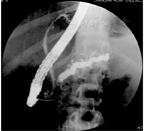

| 影像学特征性表现 | 下列任何一项:①胰管结石;②分布于整个胰腺的多发钙化;③ ERCP显示主胰管不规则扩张和全胰腺散在不同程度的分支胰管不规则扩张;④ ERCP显示主胰管完全或部分梗阻(胰管结石或蛋白栓),伴上游主胰管和分支胰管不规则扩张 | 下列任何一项:① MRCP显示主胰管不规则扩张和全胰散在不同程度的分支胰管不规则扩张;② ERCP显示全胰腺散在不同程度分支胰管扩张,或单纯主胰管不规则扩张,或存在蛋白栓;③ CT检查示主胰管全程不规则扩张伴胰腺形态不规则改变;④超声或超声内镜显示胰腺内高回声病变(考虑结石或蛋白栓),或胰管不规则扩张伴胰腺形态不规则改变 |

胰管结石根据X线可否透过分为阳性结石与阴性结石,可单独或多发存在,主要分布于胰头部[39]。对于体积较小的主胰管结石,ERCP可成功完成引流。对于最大径>5 mm的主胰管阳性结石,首选体外震波碎石术(extracorporeal shock wave lithotripsy,ESWL)治疗[40],碎石成功后可再行ERCP取石,ESWL+ERCP的主胰管结石完全清除率达70%以上,主胰管引流率达90%[39,41]。与ESWL联合ERCP治疗相比,单纯ESWL治疗可能也获得理想的结石清除及疼痛缓解[42]。ESWL术后并发症主要包括胰腺炎、出血、石街、穿孔、感染等,发生率约为6%,大多数经内科保守治疗可痊愈[43]。

主胰管狭窄的治疗原则为解除狭窄,充分引流胰液。ERCP胰管支架置入是最主要的治疗方法,辅以胰管括约肌切开、狭窄扩张等操作,疼痛缓解率可达70%以上[44]。治疗首选置入单根胰管塑料支架,可定期或根据患者症状更换支架,支架通常留置6~12个月[45]。如10Fr支架留置12个月狭窄未改善,可考虑置入多根塑料支架或全覆膜自膨式金属支架[46]。ERCP治疗时,对于主胰管严重狭窄或扭曲,导致反复插管不成功者,可以尝试经副乳头插管;对于ERCP操作失败者,可采用超声内镜引导下胰管引流术,该技术难度大、风险高,仅推荐在内镜经验丰富的单位开展[47]。